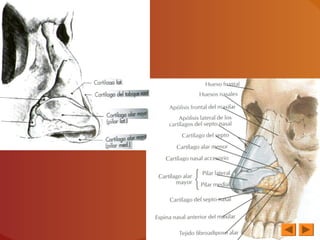

ESQUELETO CARTILAGINOSO

DE LA NARIZ

3 CARTÍLAGOS

PRINCIPALES

CARTÍLAGOS

ACCESORIOS

C. Del Tabique C. Laterales

C. Del Ala de

la Nariz

C. Vomerianos

CARTÍLAGO DEL TABIQUE

CARTÍLAGOS LATERALES

CARTÍLAGOS DEL ALA DE LA NARIZ

Describe tres segmentos:

-Externo o pilar

lateral

-Interno o Pilar

medio

- Anterior

CARTÍLAGOS ACCESORIOS

Piezas cartilaginosas

SITUACIÓN: en intervalos que separan las

narinas de

los C. laterales